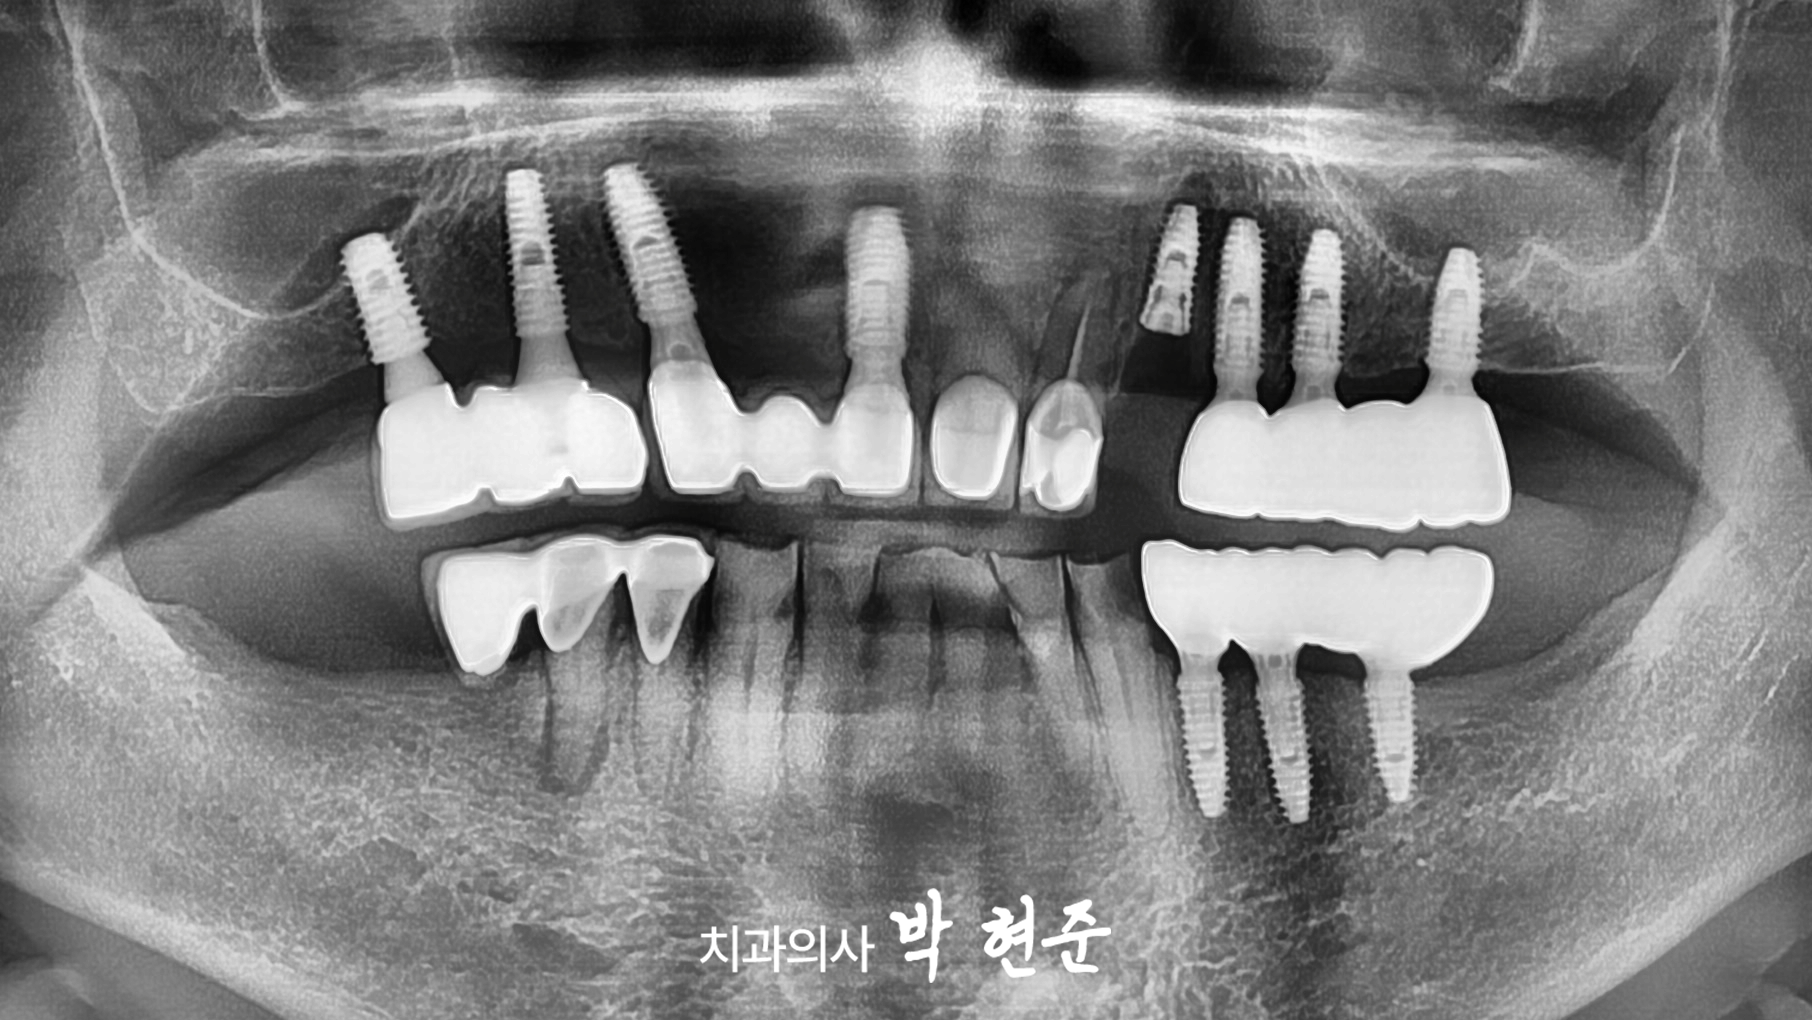

모란역치과 에서

파노라마 엑스레이도 관찰해보겠습니다.

치관부터 치근까지

넓은 범위의 이가 깨진 것으로 보이며

뿌리 끝 염증까지 진행되고 있는 것을 알 수 있습니다.

또한 이전에 신경치료를 받은

흔적이 있는 것으로 보아

살릴 수 있는 모든 방법은

다 시도했으나

이제는 자연치의 수명이

다한 것으로 판단됩니다.

2024.08.30

이로써 모든 과정이 마무리됩니다.

염증이 있던 자리도

회복되고

주변으로 뼈도 단단히 잘 결합된 것으로 보여집니다.